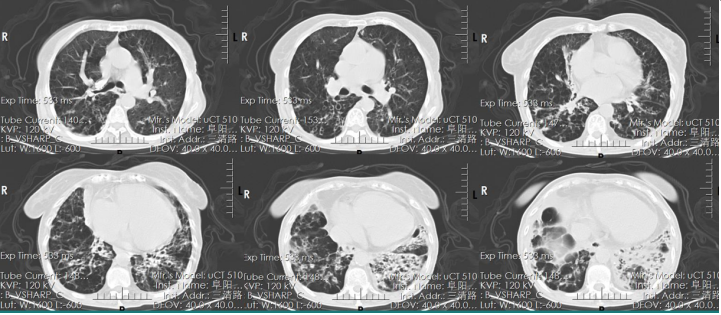

5月4日胸片示:双肺透亮度低,两下肺为甚(图2)

图2  患者入科后胸片(2024-05-04)